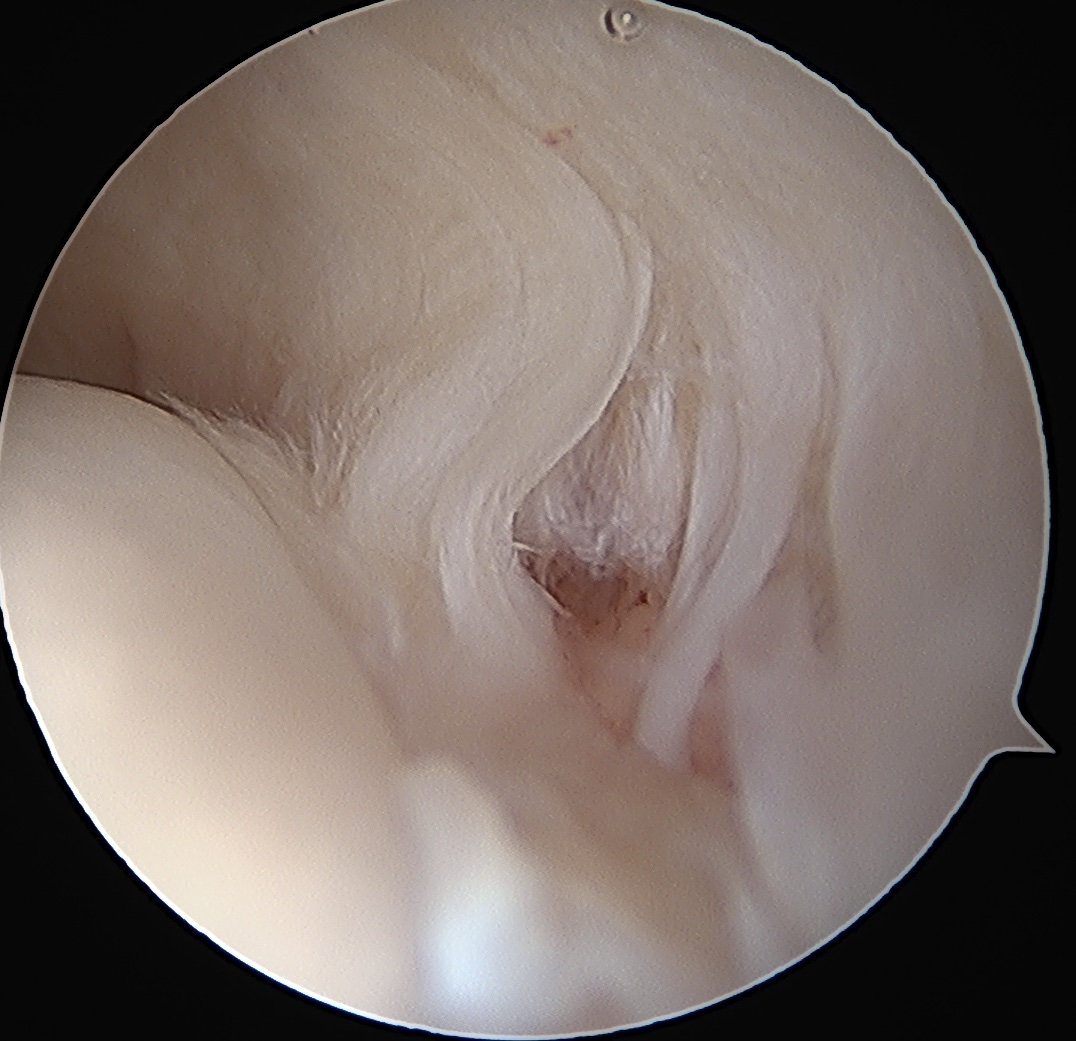

Trans-tendinous repair

Arthroscopic PASTA technique

Technique

Camera in glenohumeral joint

- debride insertion onto footprint

- 5mm anchor passed through musculotendinoous junction into footprint

- use birds beak suture to retrieve sutures / suture shuttle using spinal needle

- tie in subacomial space